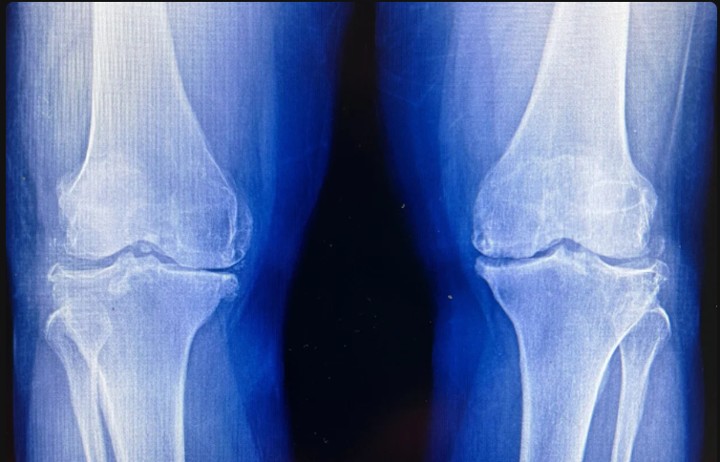

Um novo tratamento reverteu a perda de cartilagem relacionada à idade e impediu a formação de artrite após lesões no joelho em ratos. A abordagem também desencadeou a regeneração da cartilagem em tecido humano, apontando para futuras terapias que poderiam substituir a cirurgia articular. Crédito: Shutterstock

O tratamento também preveniu o desenvolvimento de artrite após lesões no joelho semelhantes às rupturas do ligamento cruzado anterior (LCA) frequentemente sofridas por atletas ou praticantes de exercícios físicos recreativos.

Os resultados do estudo sugerem que pode ser possível regenerar a cartilagem perdida devido ao envelhecimento ou à artrite com um medicamento oral ou injeção local, tornando desnecessária a substituição do joelho e do quadril.

O tratamento atua diretamente na causa da osteoartrite, uma doença articular degenerativa que afeta um em cada cinco adultos nos Estados Unidos e que custa cerca de US$ 65 bilhões em despesas diretas com saúde a cada ano.

Nenhum medicamento consegue retardar ou reverter a doença; os principais tratamentos para a osteoartrite são o controle da dor e a substituição cirúrgica das articulações afetadas.